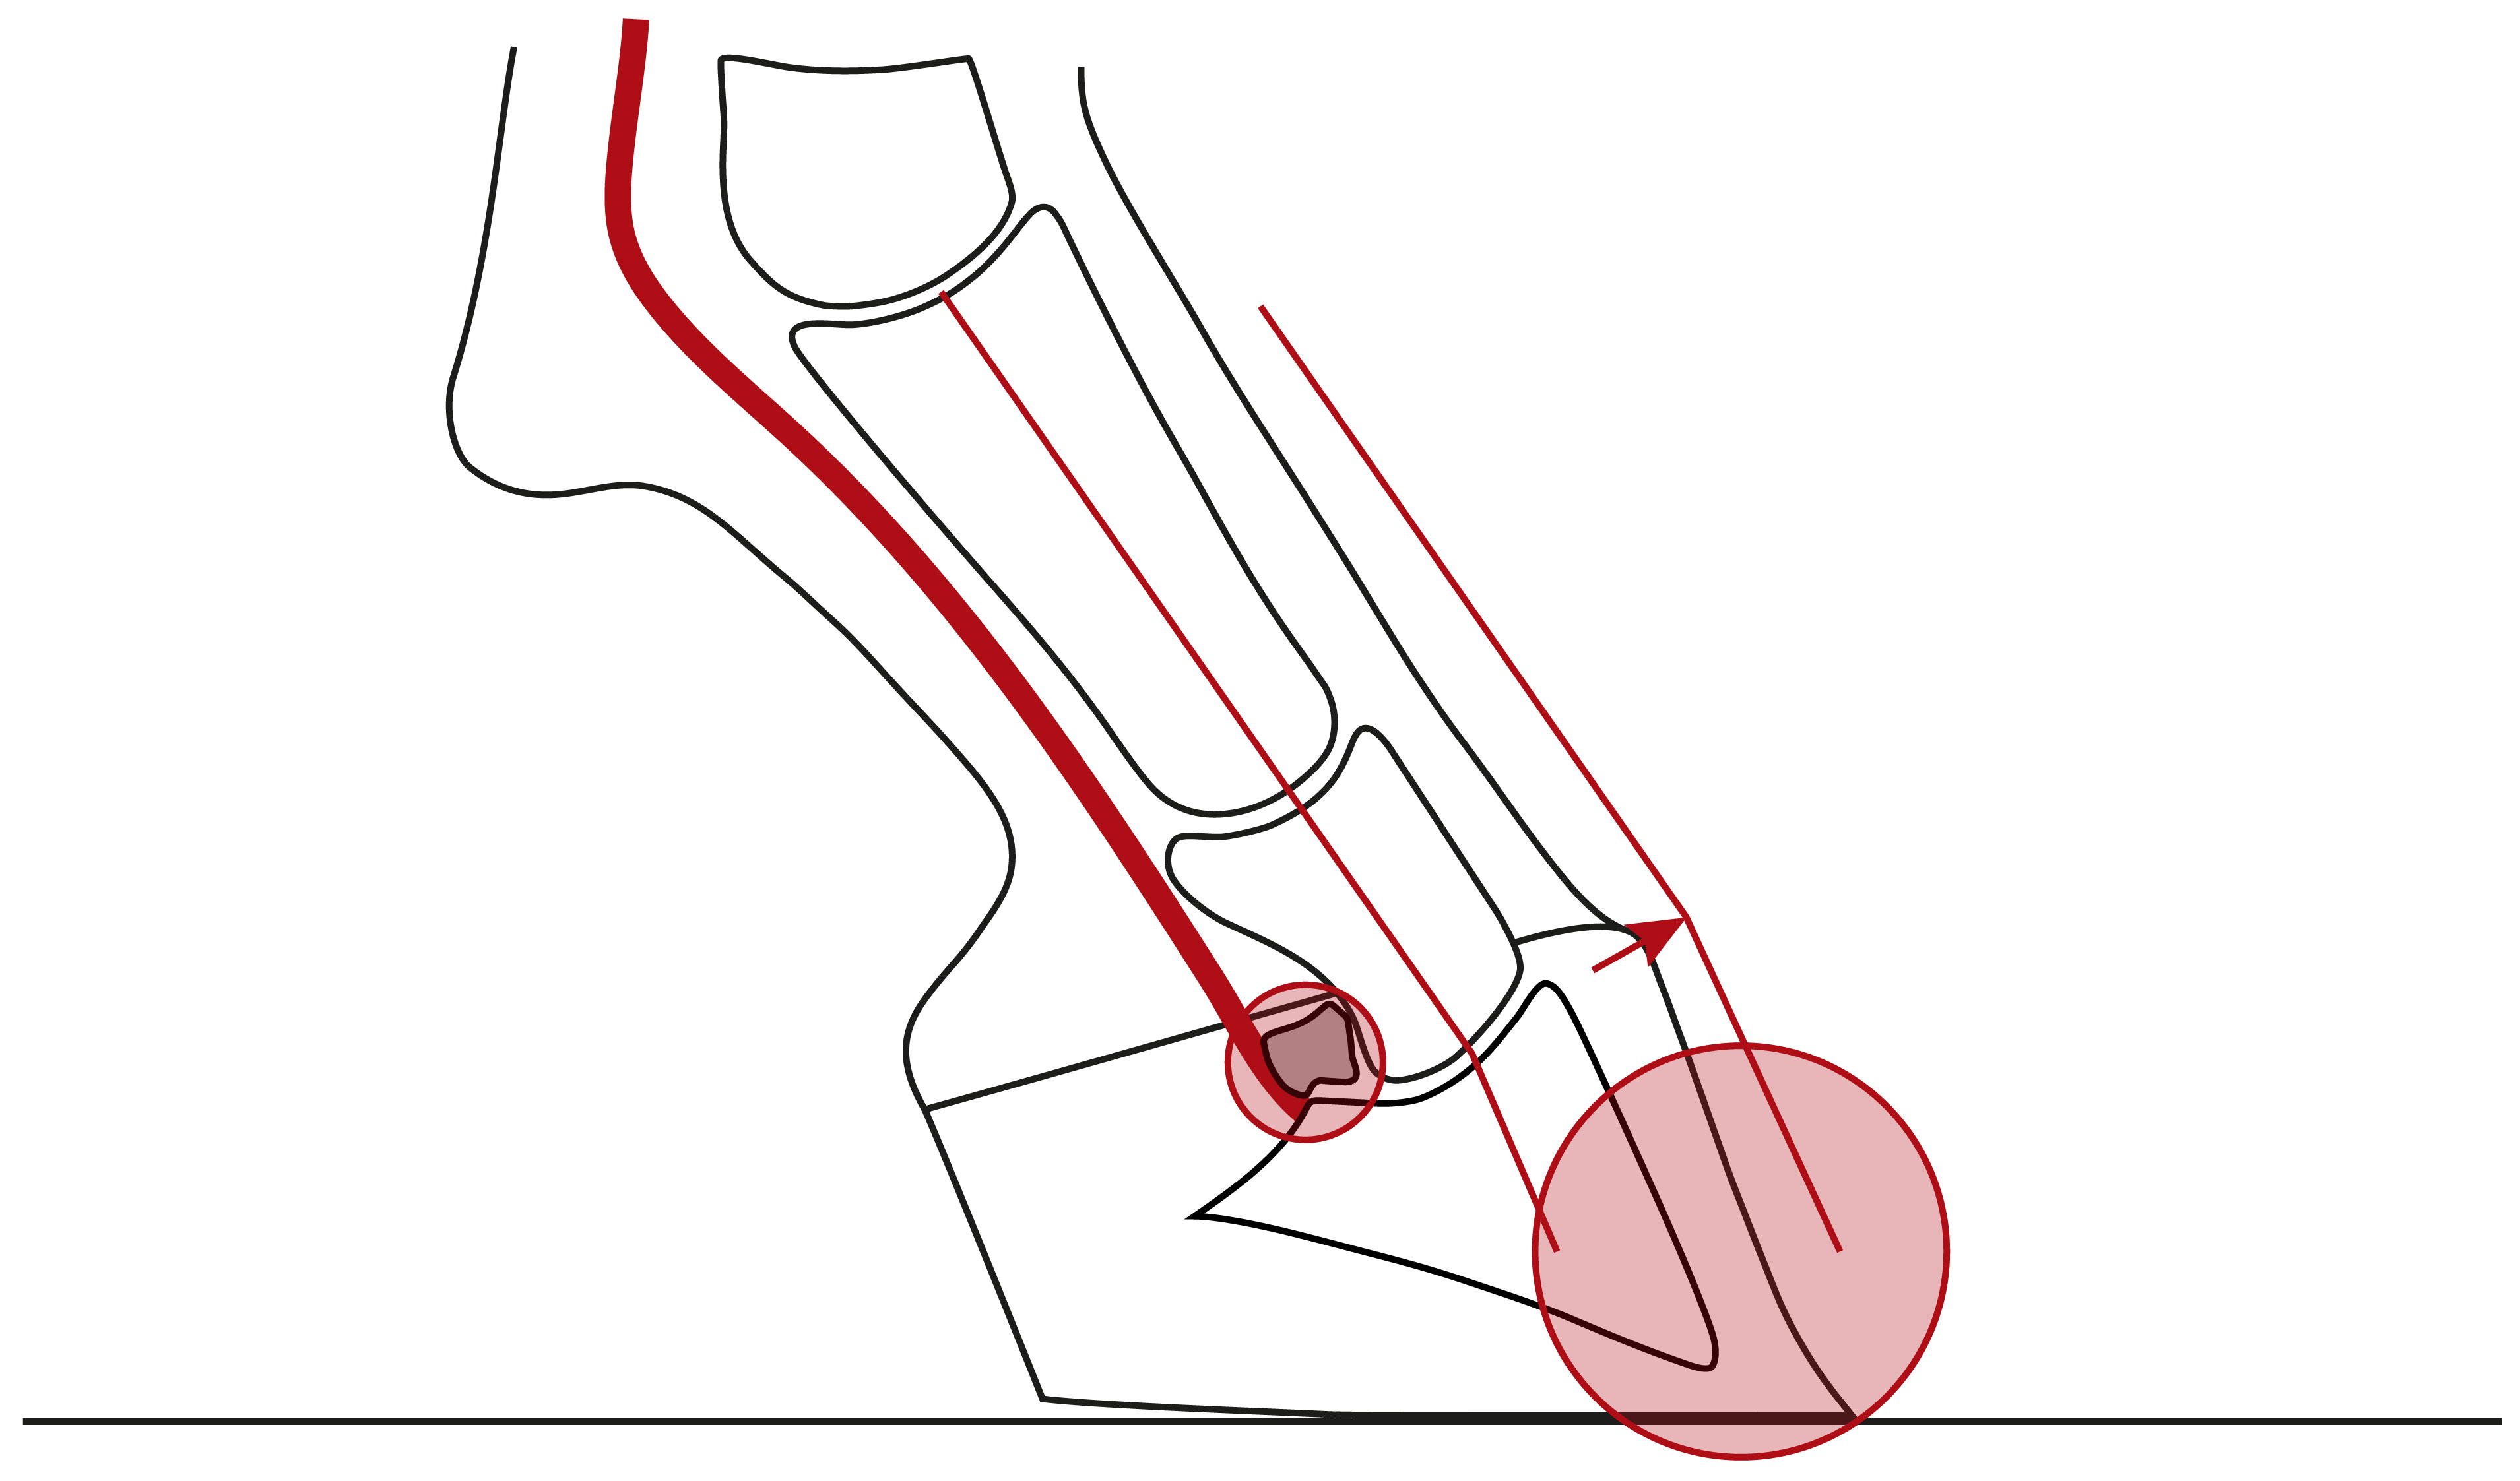

Illustration einer nach hinten gebrochenen Huf-Fessel-Achse mit einer Überstreckung von Huf- und/oder Krongelenk und einer Überlastung der Trachten, des Hufrollenschleimbeutels und ggf. der tiefen Beugesehne

Nach hinten gebrochene Huf-Fessel-Achse mit einer Überstreckung von Huf- und/oder Krongelenk und einer Überlastung der Trachten, des Hufrollenschleimbeutels und ggf. der tiefen Beugesehne.

Bei einer nach vorne gebrochenen Huf-Fessel-Achse hat der Huf einen steileren Winkel zum Boden als die Fessel, wie in den folgenden drei Illustrationen dargestellt. Wie die Analyse von etlichen Röntgenaufnahmen zeigte, liegt die Ursache dafür stets in einer Beugung des Hufgelenks, auch Flexion genannt. Das Hufbein ist also steiler zum Boden ausgerichtet als Kron- und Fesselbein.

Illustration einer nach vorne gebrochenen Huf-Fessel-Achse mit einer Beugung des Hufgelenks und einer höheren Belastung der Zehe

Nach vorne gebrochene Huf-Fessel-Achse, stets mit Beugung des Hufgelenks und einer höheren Belastung der Zehe.